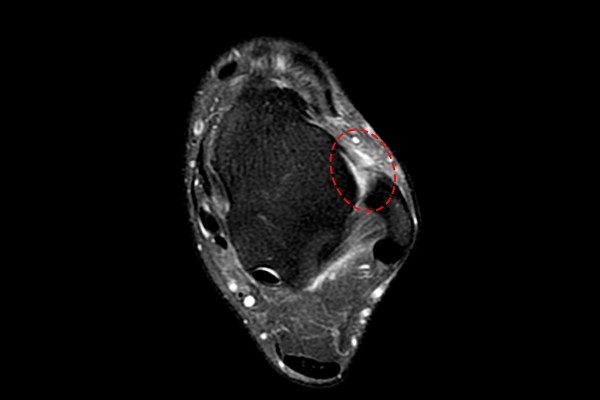

환자분의 발목 상태를 자세히 확인하기 위해서 MRI 촬영을 진행하였고, MRI에서 발목인대가 파열되어 떨어져있음이 확인되어

좌측 발목인대 파열(Lt. ankle ATFL & CFL injury)을 진단하였습니다.

환자분께 MRI 사진을 보여드리며 수술적 치료의 필요성을 설명드렸고, 환자분께서 검색으로 알아보셨던 발목인대 내시경 무매듭 직접 봉합술[내시경 올인대 봉합술](Arthroscopic-Modified Brostrom Operation (MBO))을 시행하였습니다.